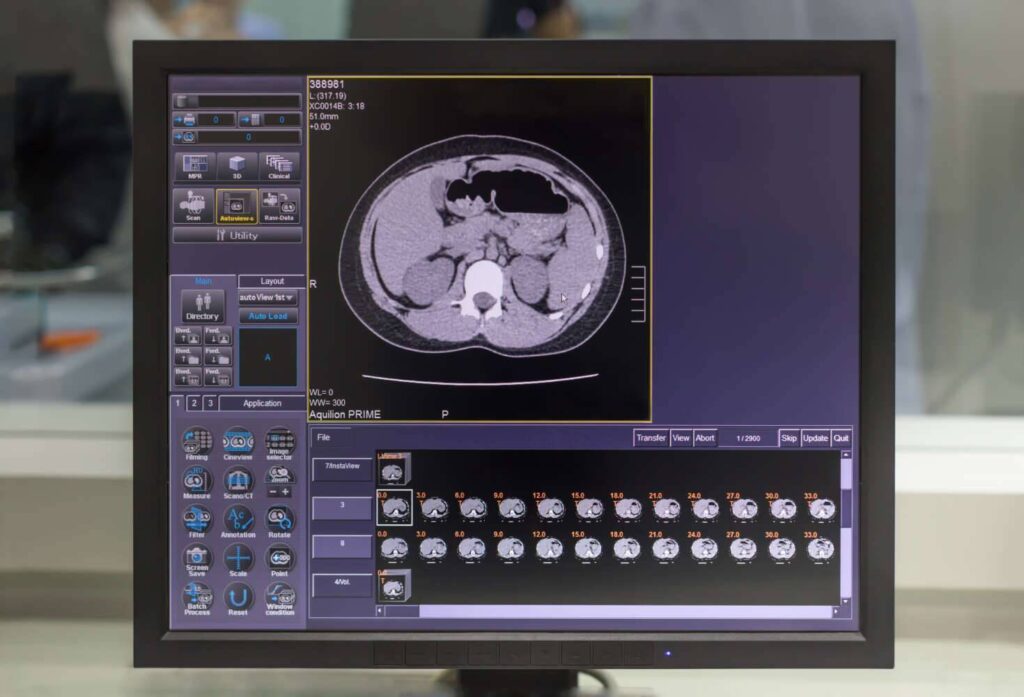

Die Magnetresonanztomographie des Abdomens, auch als MRT Abdomen bezeichnet, ist ein bildgebendes Verfahren, das magnetische Felder und Radiowellen verwendet, um detaillierte Bilder der inneren Strukturen des Bauchraums zu erzeugen. Der Bereich des Abdomen umfasst Organe wie die Leber, Milz, Bauchspeicheldrüse, Nieren, Magen, Darm.

Eine MRT Abdomen liefert besonders präzise Bilder des Bauchraums, da dieses Verfahren insbesondere weiche Gewebsstrukturen darstellen kann. Eine Magnetresonanztomographie (MRT oder auch Kernspintomographie genannt) ist ein Bildgebungsverfahren, welches die Darstellung des Körpers in mehreren Schichten und auf mehreren Ebenen ermöglicht.

Grundlage des bei der MRT aufgenommenen Bildes, ist die Ausrichtung der Atomkerne des Körpers in einem starken Magnetfeld. Während einer MRT werden sehr viele dieser Bilder von verschiedenen Schichten des Körpers erstellt, wodurch am Ende diese Einzelbilder zu einem 3-dimensionalen Bild zusammengesetzt werden können. Für Patienten ist dieser Vorgang vollkommen ungefährlich und schmerzfrei.

Was kann man auf einer MRT des Abdomens sehen?

Auf einer MRT-Aufnahme sind insbesondere die Organe im Bauchraum sichtbar, da Weichteile in einer MRT sehr gut abgebildet werden können.

Zu sehen und später im weiteren Verlauf beurteilbar sind:

- Leber, Gallengängen, Bauchspeicheldrüse, Nieren und Nebennieren mit Harnleiter, Milz, Becken

Durch die detailreichen Abbildungen können Veränderungen der Organe festgestellt werden, die auf bestimmte Krankheiten schließen lassen – so können beispielsweise Entzündungen oder Gewebsveränderungen im Bauchraum festgestellt werden.

Es kann zwischen gut- und bösartigen Tumoren unterschieden werden. Dies ermöglicht eine genaue Diagnose, woraufhin ein schnelles und geeignetes Therapieverfahren angesetzt werden kann.